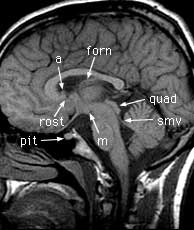

Findings: Nodule (a) in the inferior left lateral ventricle above the rostrum (rost) of the corpus callosum. Pituitary gland (pit). Mamillary body (m). Body of the fornix (forn). Quadrigeminal plate (quad). Superior medullary velum (smv).